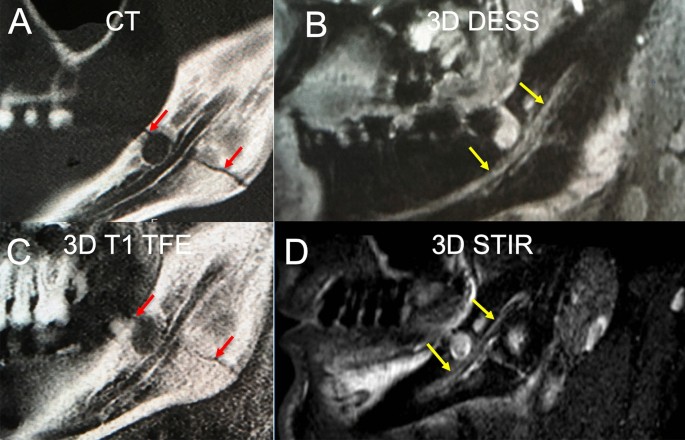

In this clinical case a slightly displaced mandible fracture is illustrated (red arrows). The CT (A) and the 3D T1 FFE sequence (C) revealed the osseous continuity disruption with involvement of the mandibular canal with comparable accuracy. However, no conclusions regarding the condition of the IAN can be drawn as it is not visualized sufficiently. The DESS sequence allows for precise depiction of the IAN (B). The STIR sequence shows an increase in signal intensity within the IAN as well as an enlarged nerve diameter (D). The nerve continuity is preserved (yellow arrows).

Fifteen IANs involved in mandible fractures were included in this study. Serving as controls, 15 IANs of the contralateral side were included, as well as a second control of 30 IANs of healthy, age-matched volunteers. Using the 3D T1 FFE sequence and the 3D STIR sequence, the fracture course and potential IAN involvement could be visualized. The 3D T1 FFE sequence showed precise hard tissue visualization with high spatial resolution. The 3D STIR sequence allowed for edema detection within the IAN. The 3D DESS sequence provided reliable depiction of nerve topography. In contrast to MRI, conventional dental imaging (CT and CBCT) only allowed for the depiction of cortical boundaries within the mandible. Whereas, the STIR sequence allowed for qualitative discrimination of the nerve.

Dislocation comparison of 3D T1 FFE sequence and CT

The dislocation measurements at the punctum maximum of posttraumatic cortical deviation yielded comparable results for the CT and the 3D T1 FFE sequence (3.1 vs. 2.6 mm, p = 0.707). However, a tendency to underestimate the dislocation extent was apparent in the 3D T1 TFE sequence (Fig. 1A). A high ICC was given between the two readers (ICC = 0.999, p < 0.001).